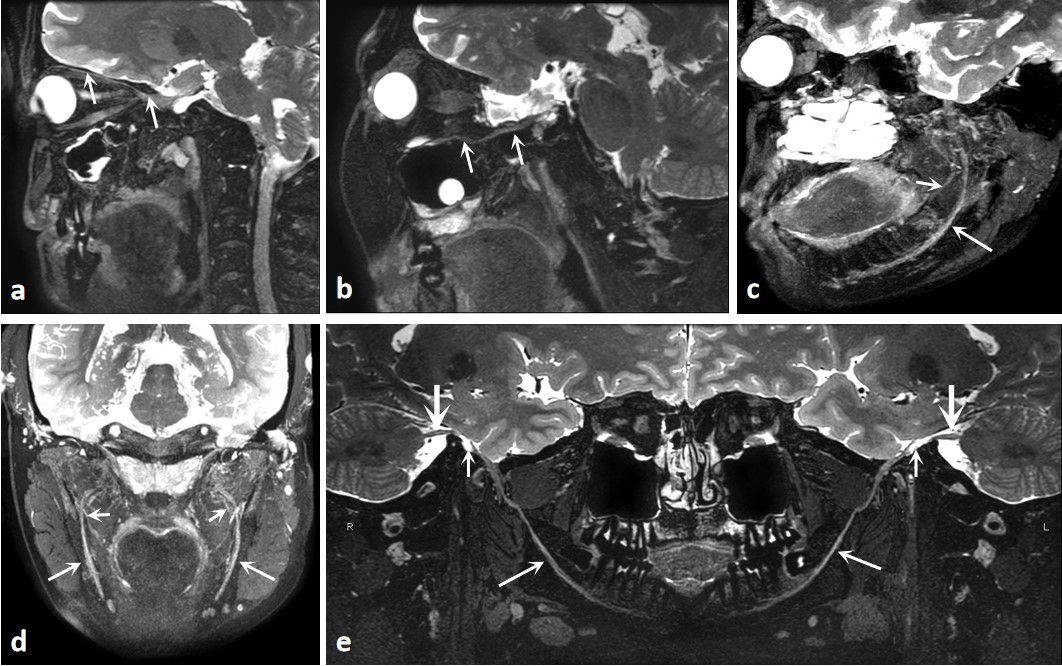

(1)正常三叉神经的MRI成像。

A 3D T2WI-CUBEfs重建图像显示了眼神经(箭头);B 3D T2WI-CUBE fs重建图像显示上颌神经(箭头);C,D 3D T2WI-CUBE fs重建图像显示了下颌神经,下牙槽神经(长箭头)和舌神经(短箭头)的分支;E 3D T2WI-CUBE fs重建图像显示了三叉神经下颌支的完整图像。